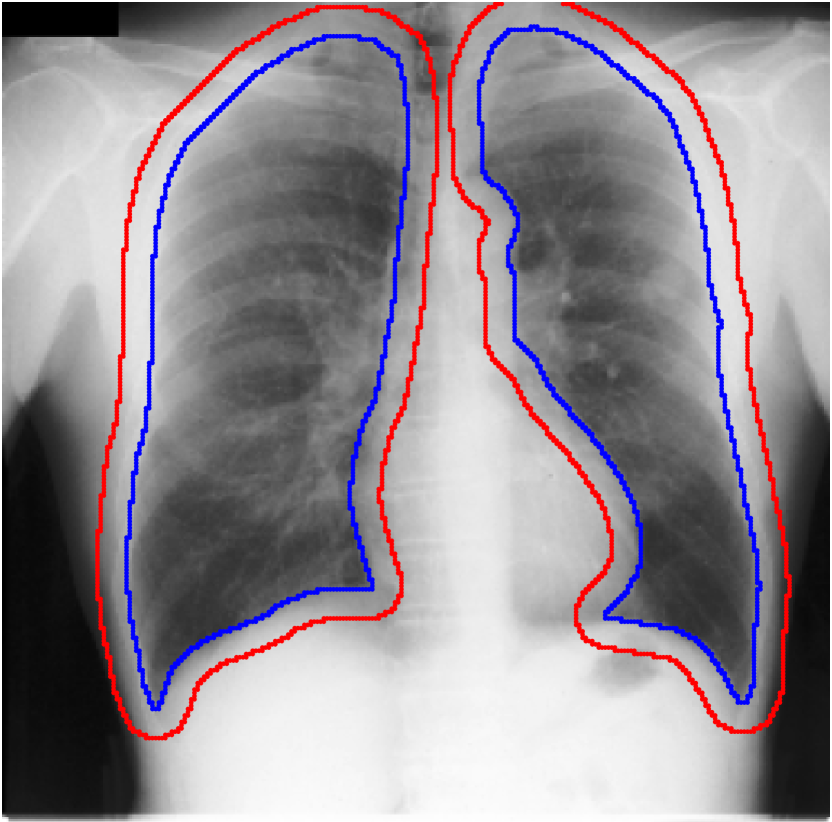

A few existing segmentation label noise approaches (Zhu et al., 2019; Zhang et al., 2020b; a) directly apply methods in classification label noise. However, these methods assume the label noise for each pixel is i.i.d. (independent and identically distributed). This assumption is not realistic in the segmentation context, where annotation is often done by brushes, and error is usually introduced near the boundary of objects. Regions further away from the boundary are less likely to be mislabeled (see Fig. 1(c) for an illustration). Therefore, in segmentation tasks, label noise of pixels has to be spatially correlated. An i.i.d. label noise will result in unrealistic annotations as in Fig. 1(b).

We propose a novel label noise model for segmentation annotations. Our model simulates the real annotation scenario, where an annotator uses a brush to delineate the boundary of an object. The noisy boundary can be considered a random yet continuous distortion of the true boundary. To capture this noise behavior, we propose a Markov process model. At each step of the process, two Bernoulli variables are used to control the expansion/shrinkage decision and the spatial-dependent expansion/shrinkage strength along the boundary. This model ensures the noisy label is a continuous distortion of the ground truth label along the boundary, as shown in Fig. 1(c). Our model also includes a random flipping noise, which allows random (yet sparse) mislabels to appear even at regions far away from the boundary.

Table 1 shows the segmentation results of different methods with synthetic noisy label settings on JSRT , ISIC 2017 and Brats 2020 dataset. Note that QAM cannot be applied to Brats 2020 dataset because their network is designed for 2D only. We compare DICE score (DSC) on testing sets (against the clean labels). For each setting, we train 5 different models, and report the mean DSC and standard deviation. In and , where biases show up in noisy labels, the proposed method outperforms the baselines by a big leap in total case. The compared methods, however, only work when little bias is included, like . is equivalent to setting in our Markov model, resulting in . We also test the proposed method on real-world label noise, results shows in Table 2. Figure 5 shows examples of label correction results. We provide more qualitative results in the Appendix A.4.